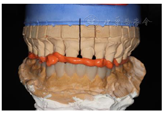

制作上颌活动

垫:调磨过锐牙尖,取印模,正中关系位记录

关系,制作上颌活动

垫,调磨使后牙功能尖均匀接触,侧方

无干扰。此病例

垫做在上颌,因其下前牙牙冠短,不至于引起前伸

干扰,引起关节后移(图14,图15)。戴用